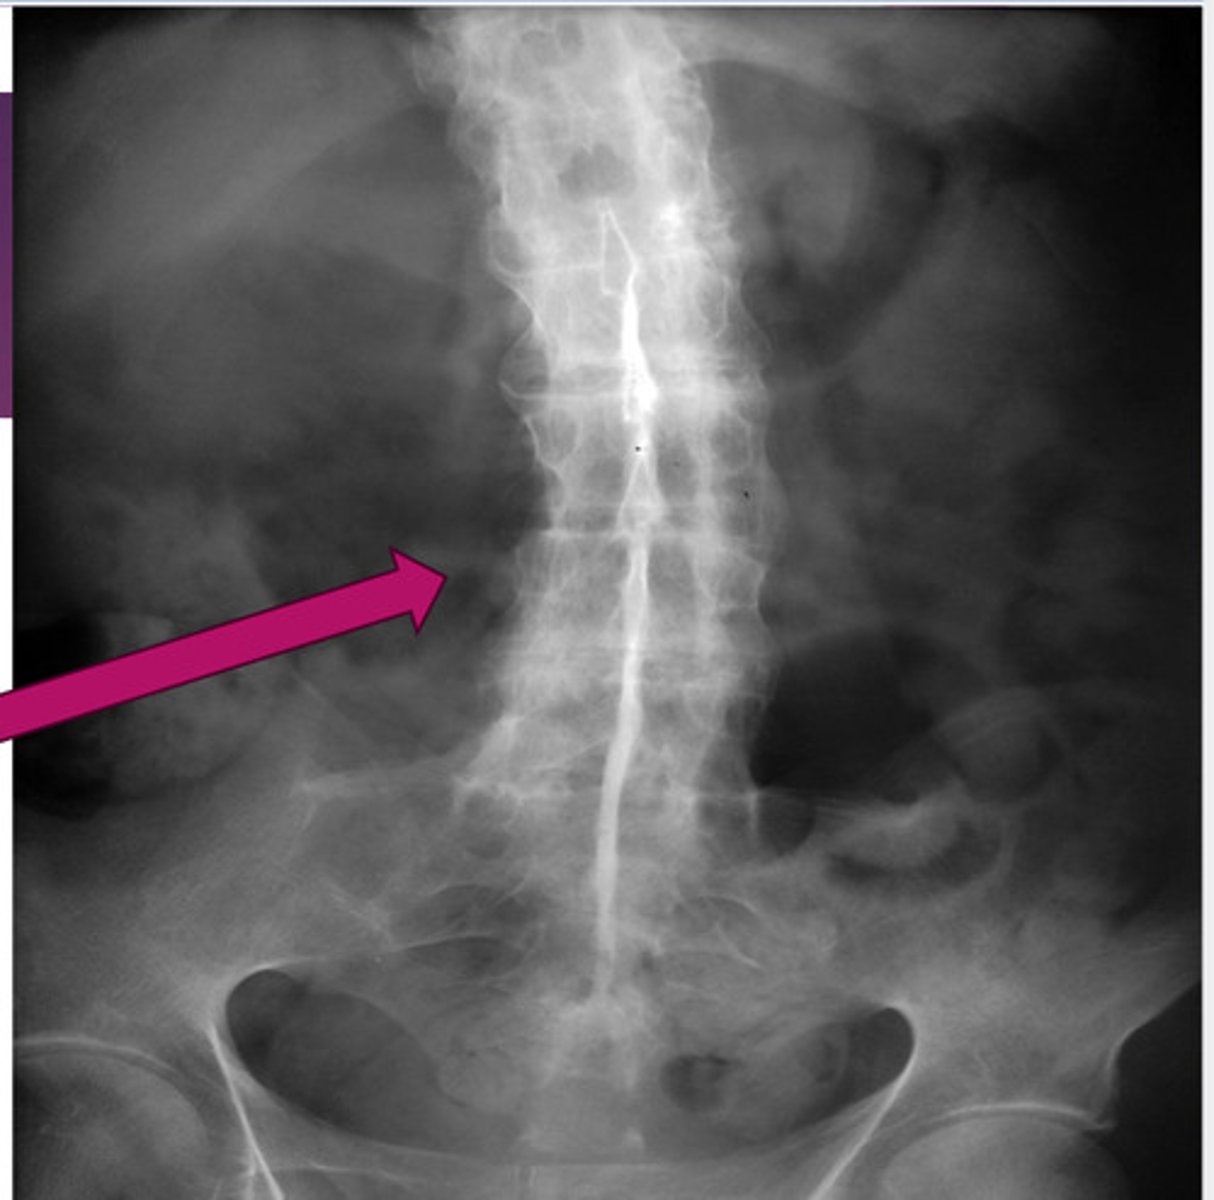

hallmark of ankylosing spondylitis

fusion of lumbar spine & sacroiliac joints (sacroilitis)

bamboo spine ("dagger sign" on AP projection)

ankylosing spondylitis; no spaces b/w vertebrae